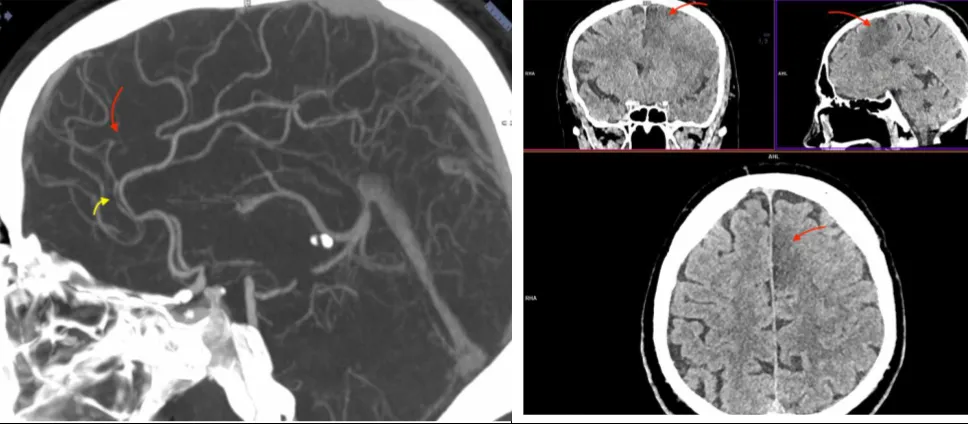

Рисунок 1. Результати нативної МСКТ голови.

При нативній МСКТ голови виявлені ознаки досить великого свіжого вогнища інфаркту в ділянці базальних гангліїв (голівка хвостатого ядра, шкарлупа та внутрішня капсула) та лобно-острівцево-скроневій області ліворуч, без ознак латерального зміщення серединних структур мозку. Оцінка за ASPECTS = 5 балів.